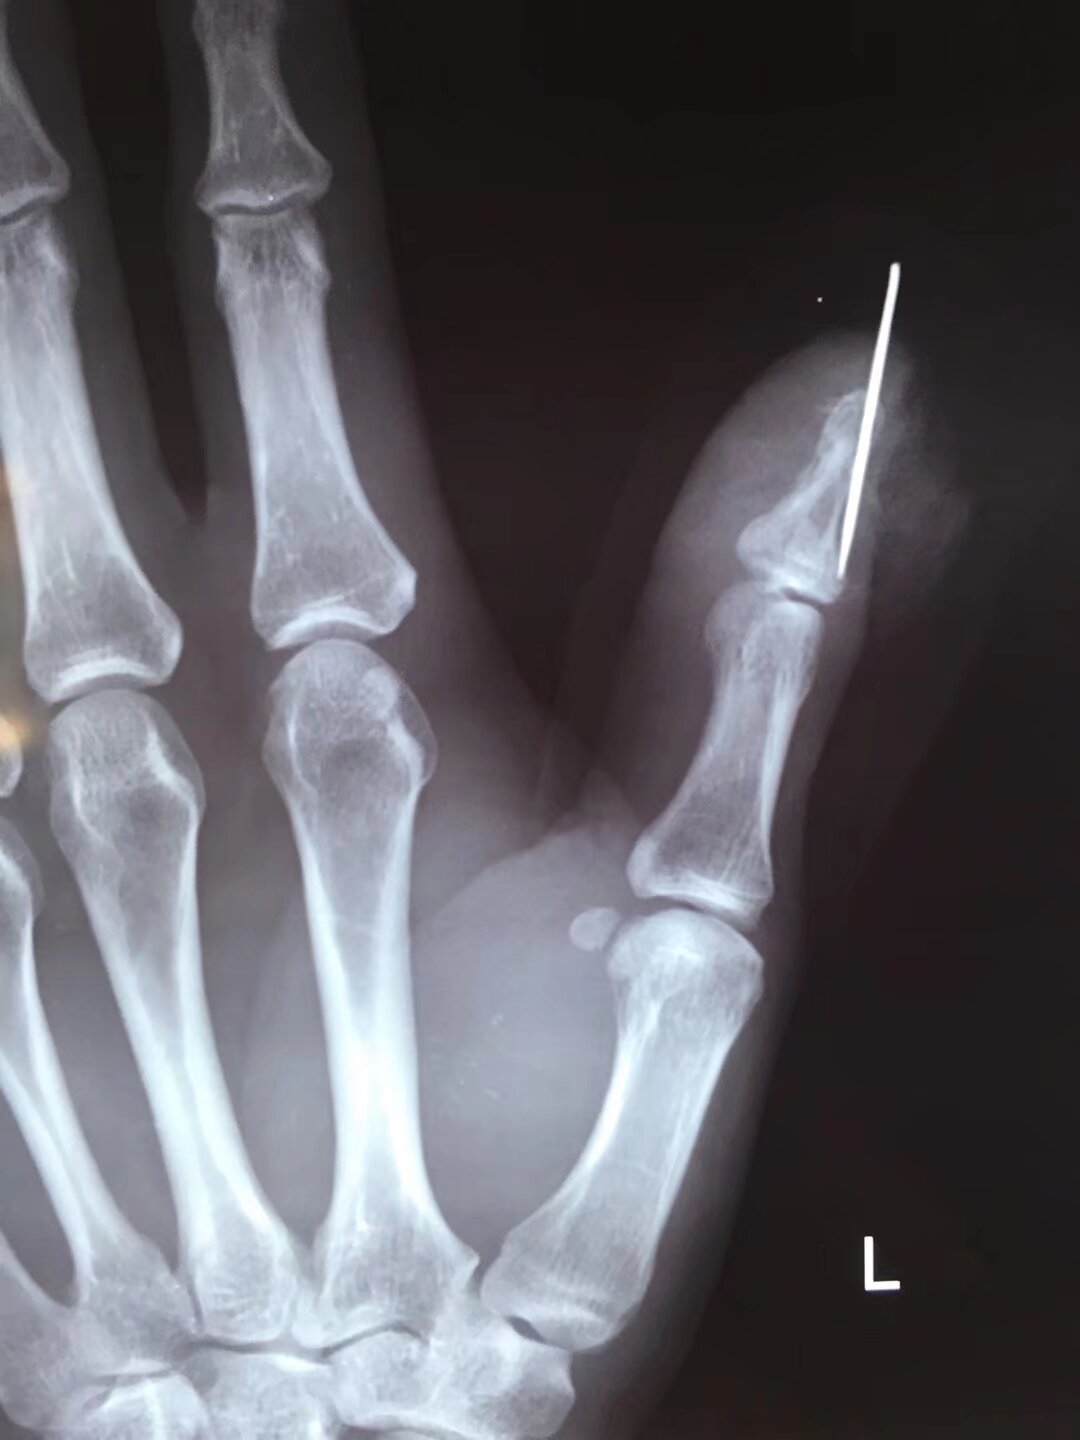

指骨骨折后,克氏针固定是临床常用的治疗方法,尤其适用于手法复位困难或不稳定的骨折,其应用主要体现在以下方面:

2常用固定方式

- 单根克氏针固定:适用于简单横形骨折或斜形骨折,从骨折一端穿入,穿过骨折线至另一端,直接固定断端。

- 交叉克氏针固定:对于斜形、螺旋形或粉碎性骨折,采用两根克氏针交叉穿入骨折端,增加固定稳定性,防止旋转或侧方移位。

- 髓腔内固定:从指骨远端或近端髓腔穿入克氏针,贯穿骨折线,利用髓腔支撑作用固定,适用于长斜形或短缩倾向明显的骨折。

2克氏针相关问题

- 克氏针松动或移位:固定过程中若针的位置或深度不合适,或患者过早活动、负重,可能导致克氏针松动、退出,甚至移位,影响骨折固定效果,造成骨折再移位。